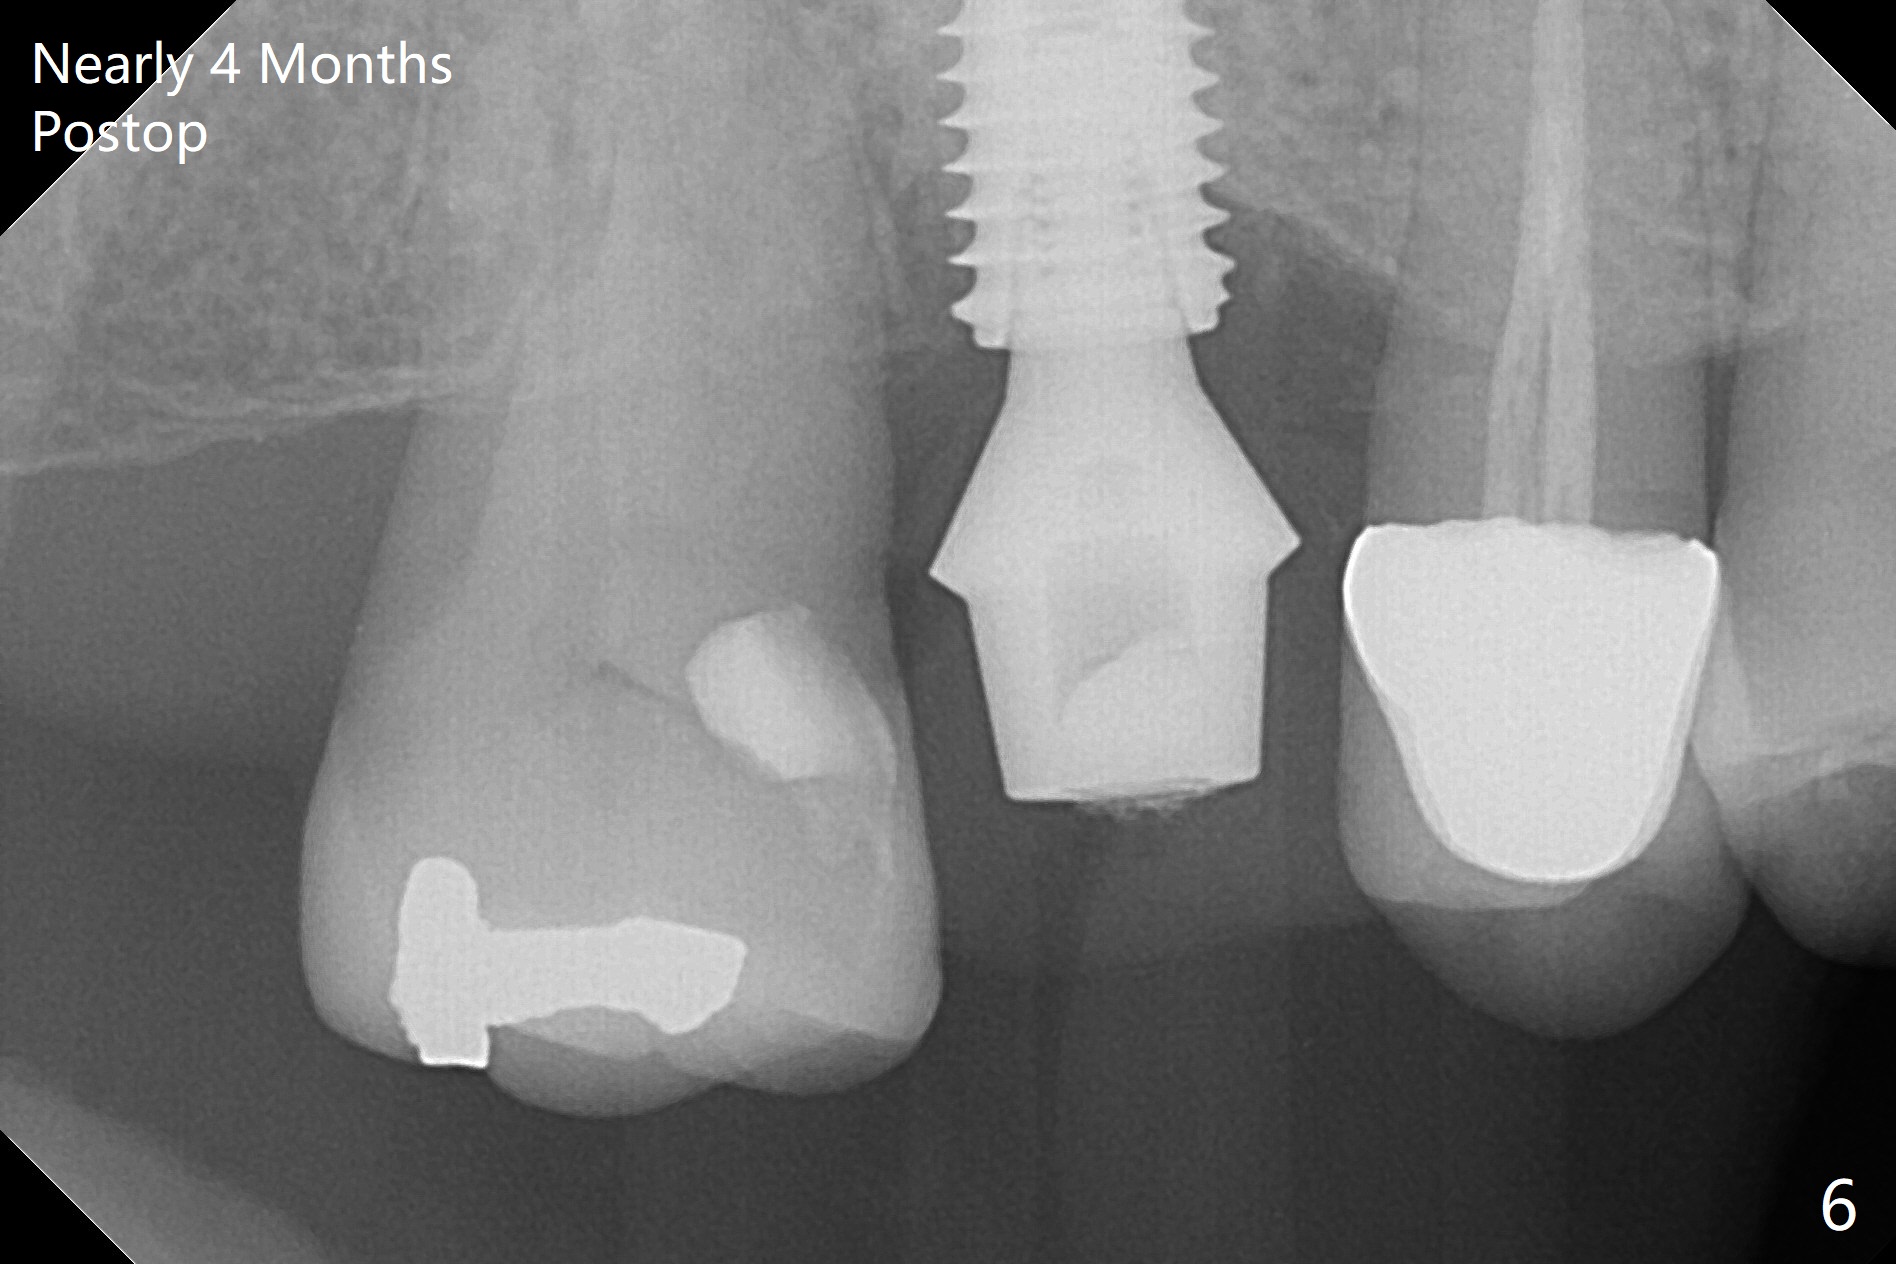

A 5x10 mm implant is placed at #3 according to drill sequence except 4.5x10 mm drill having to be used (plan: underdrilling using 4.0x10 mm as the last one) because of dense bone. Insertion torque is >50 Ncm. Although the implant apparently penetrates the sinus floor (Fig.1), the bottom of the osteotomy is intact before implant placement. In addition, the 12 mm bone trimmer does not touch the septal bone, while 2.2x8.5 mm drill starting to remove bone. In spite of using the largest cementation abutment (6.5 mm), the buccal (Fig.2) and palatal sockets with bone graft (*) are exposed. An immediate provisional (Fig.3 P) is fabricated for remaining socket closure. The buccal gingiva appears to have receded relative to the abutment margin nearly 4 months postop (Fig.4). The mesial crestal bone defect seems to be repairing (Fig.5 (*),6). The abutment later changes to a 5.7x5.5(2) mm one with margin modification buccomesiolingually before impression.